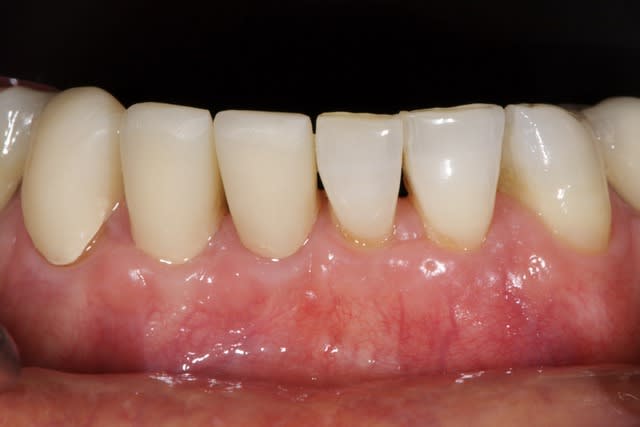

Je stressais pas mal sur ce cas quant à la réussite du conj. enf. avec lamb. tracté coronairement. Mais le résultat est acceptable je pense, car on partait de loin.

Juxta en vest, supra en linguale, et infra en proximal.

Dans le cas d'un biotype fin vest peut-être , quoi que en pratique la limite supra/juxta est parfois minime. Ici le biotype est devenu épais, donc c'est juxta avec CCC ce qui est bien plus agréable pour le parodonte.

Il faut aussi voir ici l'anatomie des dents qui rendait les préparations délicates au niveau périphérique.